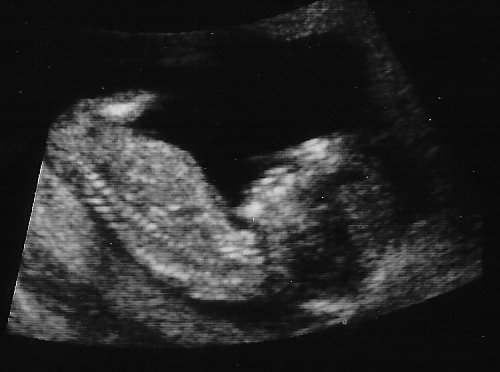

애기 초음파 사진

현재 아내가 임신 18주 6일째입니다. 그 동안 산부인과에 가서 초음파 사진을 몇 장 찍었는 데, 그 중에서 가장 잘(?) 나온 사진 하나를 올려 봅니다. 위 사진은 2월 말(임신 12주 정도 됐을 때)에 찍은 사진입니다. 사진 오른편이 머리이고, 아래 보이는 것이 척추입니다. 지금은 애기가 커서 한 화면에 다 안나온다네요.